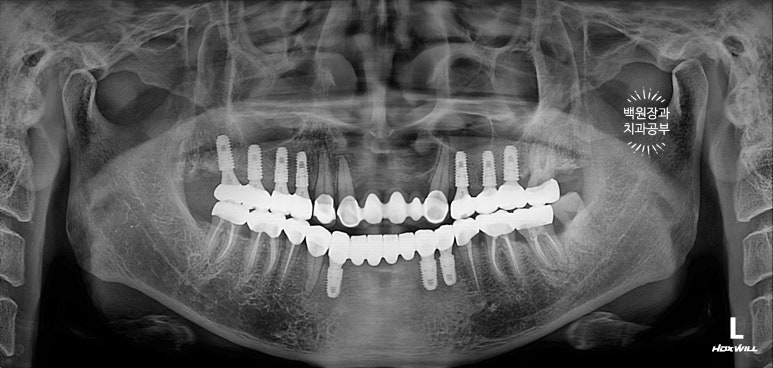

치과용 파노라마 엑스레이를 보시면 더 드라마틱한 변화를 느끼실 수 있어요.

다수의 치아가 씌워지고, 임플란트로 회복되어 마치 사이보그같은(?!) 느낌이 들긴 하지만,

정갈하게 치료가 잘 된 느낌입니다.!!!

임플란트의 위치가 적절히 배치되어 있어, 임플란트에서 크라운까지 이어지는 emergency profile이 예술이네요.

들쭉날쭉한 치아 없이 조화로운 교합이 형성되어 있는 것을 보실 수 있을거에요.

교합평면도 가지런하게 형성되어 보입니다.